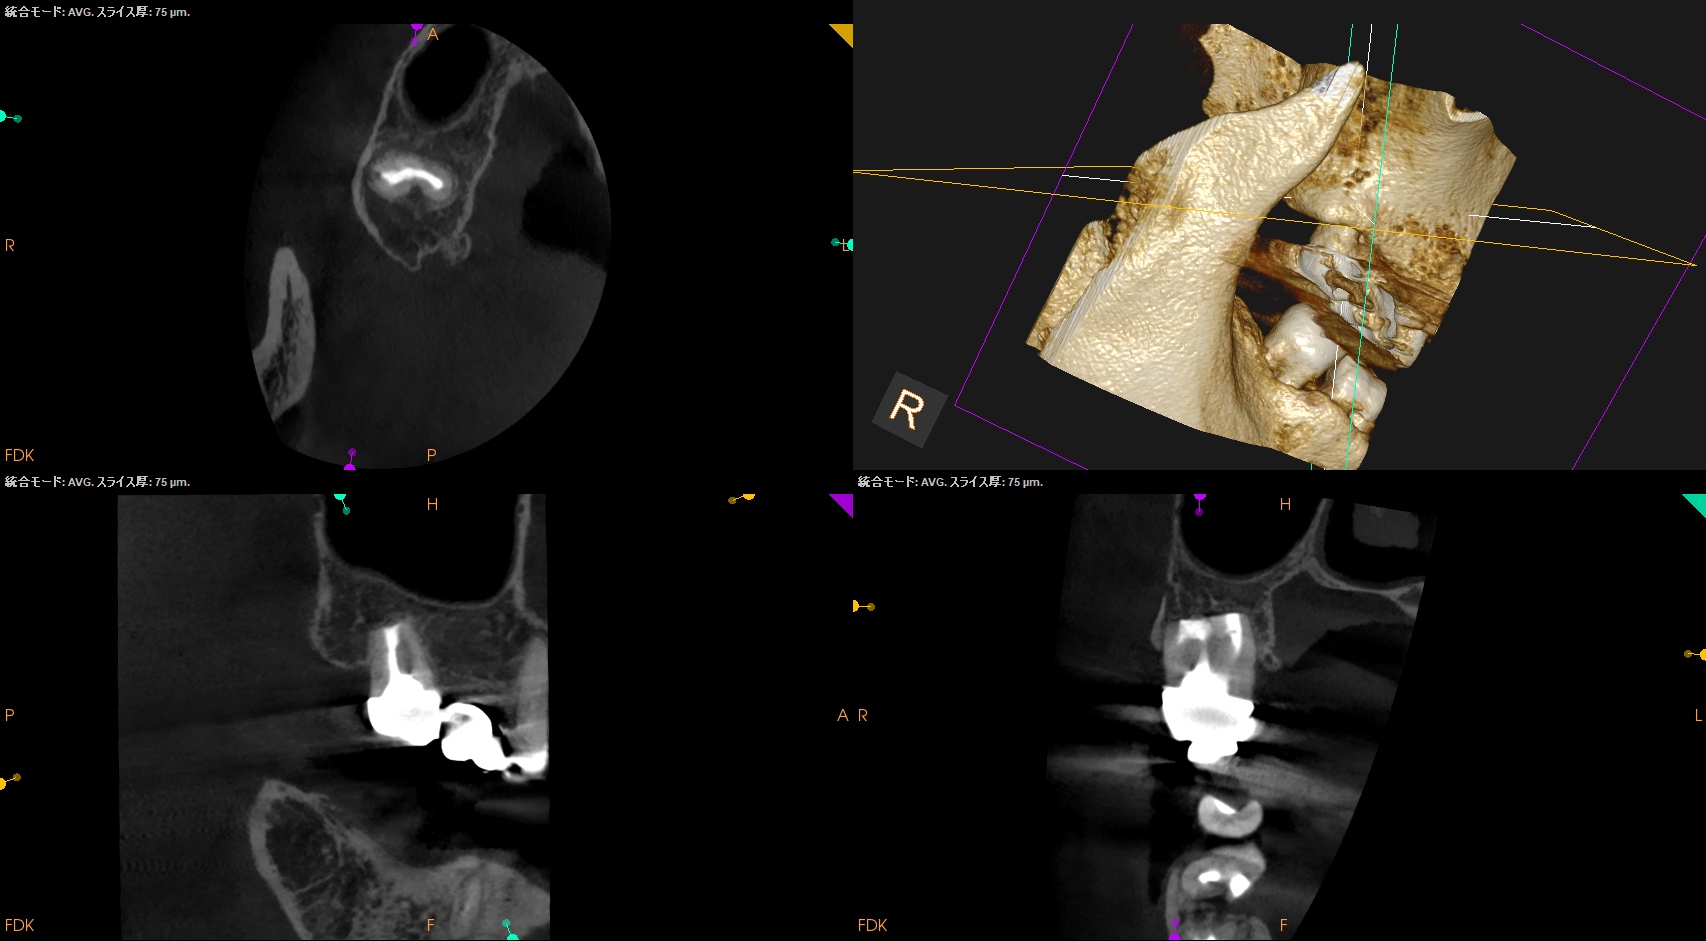

Intentional Replantationから7年が経過していた。

#2 Intentional Replantation 7yr recall(2025.12.9)

問題はない。